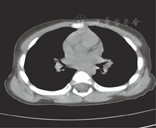

患儿,男,20个月,咳喘1 d,加重半天入院。查体:T 36.5 ℃,P 120次/min,R 56次/min,神志清楚,呼吸急促,口周微绀,可见鼻扇及三凹征,双侧胸廓对称,呼吸运动一致,听诊双肺呼吸音对称,闻及大量喘鸣音,叩诊呈清音。心音有力,律齐,心率120次/min,各瓣膜区未闻及病理性杂音。既往史:自生后7个月开始有4次反复咳喘史,胸片均提示支气管肺炎,给予抗感染及对症治疗后病情有所好转。此次入院辅助检查:胸片提示左肺可见少许斑片影,血气分析:pH 7.35,PCO2 48 mmHg(1 mmHg=0.133 kPa),PO2 40 mmHg,Lac 0.3 mmol/L,BE -5 mmol/L,K+ 3.6 mmol/L,Ca2+ 1.18 mmol/L,GLU 4.3 mmol/L,Na+ 143 mmol/L。初步诊断:肺炎,Ⅰ型呼吸衰竭。经吸氧,抗感染,保持气道通畅,平喘化痰等对症治疗后效果不佳,咳喘重,故进一步完善多层螺旋CT检查(图1、图2),提示右上叶支气管下方见异常分支支气管,供应右上叶肺段,余左右支气管管腔通畅,未见狭窄及阻塞。临床诊断:气管性支气管(额外型)。

多层螺旋CT操作快,无创伤及痛苦,没有并发症,其呼吸道的三维重建成为诊断气管性支气管最佳检查方法,文献报道其检出率明显高于支气管内镜[3],它可以明确诊断及分型,还可以进一步了解气管狭窄的位置和程度,为临床诊断提供了依据。本文报道的患儿属于额外型,未发现其他先天发育异常。